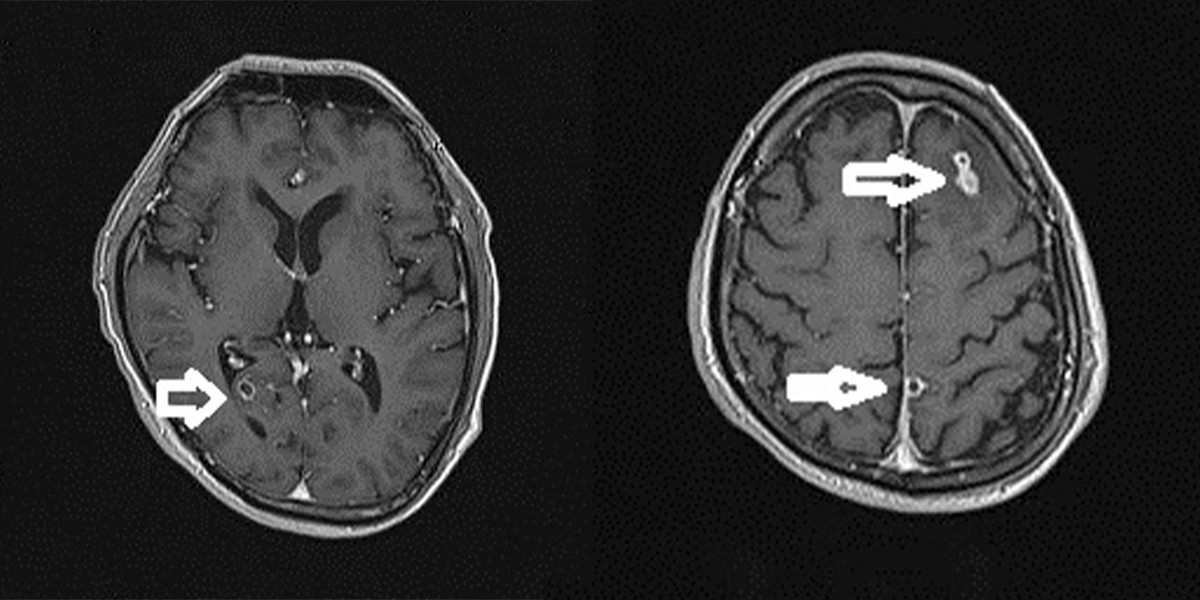

Trước khi vào viện, chị xuất hiện triệu chứng đau đầu dữ dội, xuất hiện nhiều cơn co giật mặc dù đã kiểm soát bằng thuốc chống động kinh. Chị được các bác sĩ chuyên khoa Ngoại Thần kinh chỉ định làm cận lâm sàng. Hình ảnh chụp cổng hưởng từ sọ não tiêm chất tương phản cho thấy, người bệnh bị tổn thương não do sán. Kết quả xét nghiệm giải phẫu bệnh là mô não có nhiều ổ viêm hạt, trung tâm chất hoại tử, bao quanh lympho, đại bào nhiều nhân, tương bào và tế bào sợi. Bác sĩ kết luận người bệnh tổn thương viêm não do nang sán.

Hình ảnh sán làm tổ trong não.

- Chụp MRI hoặc CT Scan thấy nang sán ký sinh ở não, hình ảnh các nang sán não có thể gặp một hay nhiều giai đoạn khác nhau.

Trước đó, Bệnh viện Quốc tế Vinh tiếp nhận trường hợp ông H.V.P 65 tuổi, trú tại Đô Lương, Nghệ An nhập viện trong tình trạng đau đầu và lên cơn co giật (động kinh). Với các triệu chứng lâm sàng của người bệnh, kèm theo kết quả chụp cắt lớp vi tính (CT), bác sĩ phát hiện nốt vôi hóa nhỏ trong nhu mô não hai bán cầu đại não, có phù não xung quanh, Bác sĩ nghi ngờ ông P. mắc bệnh kén sán não ở người. Để chẩn đoán xác định bệnh lý, người bệnh được chỉ định chụp cộng hưởng từ (MRI) sọ não có tiêm thuốc và thực hiện xét nghiệm ELISA.